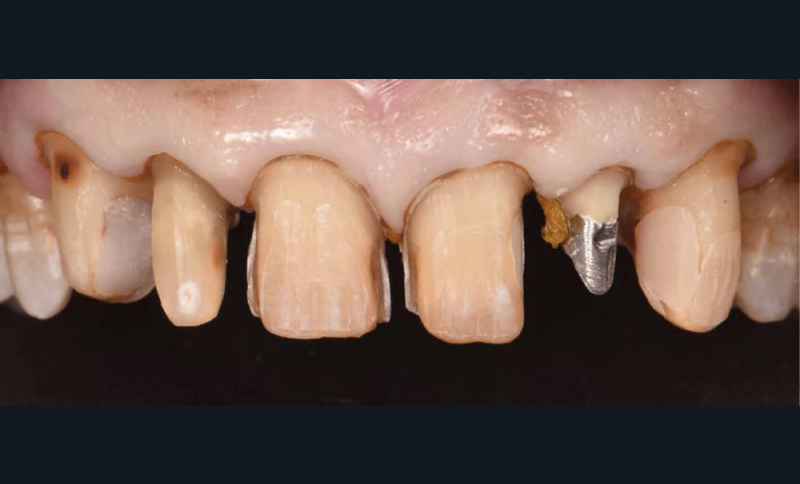

La deuxième étape comprend la préparation dentaire et la réalisation de restaurations provisoires (Voco Structur®) issues du wax-up. On traitera les lésions carieuses et les composites déjà présents seront remplacés. Les préparations sont donc guidées par ces restaurations de manière à n’avoir qu’une seule interface « céramique/dent » (fig. 3). On note donc des facettes à retour palatin, une couronne périphérique, et des couronnes ¾. La restauration corono-radiculaire sur 22 n’est pas déposée pour deux raisons : aucune lésion apicale n’est présente sur la dent et le patient est porteur d’une prothèse valvulaire aortique contre-indiquant tout retraitement endodontique (haut risque d’endocardite infectieuse).